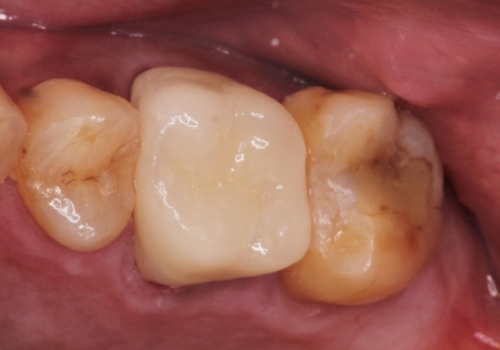

- 治療計画

根管治療を行ったのち、症状改善を認めオールセラミッククラウンにて修復治療を行いました。

根管治療にはラバーダムシートをつけて行うことが大切です。マイクロスコープを使用し治療を行いました。治療後、歯の痛みは消失し、とても満足していただきました。

根管治療を行った歯は、再発防止や残された歯質を守るため、クラウンによる補綴治療が必要となります。